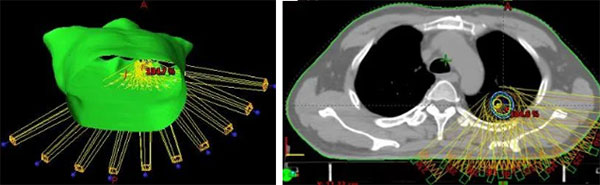

肺癌的放射治疗